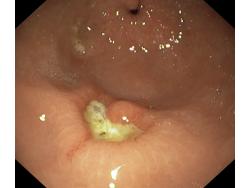

Wrzód trawienny